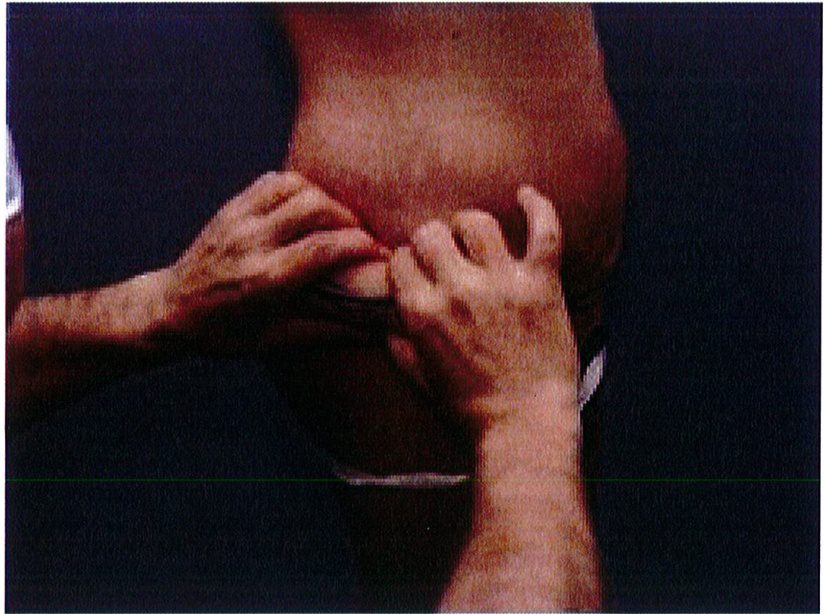

Đối tượng lý tưởng cho phẫu thuật này là bệnh nhân có vùng da và mô mềm vùng thắt lưng/mông dư thừa nhưng mông dẹt và gần như không có điểm hình chiếu. Tiêu chuẩn này có thể được xác định bằng cách dùng hai tay sờ và véo da đồng thời (Hình 2). Quy

Bằng cách sờ và véo da đồng thời bằng hai tay (hình 2) ở vị trí đường nách giữa, chúng ta đánh dấu phần da tiếp xúc với ngón trỏ và ngón cái, nối chúng với nhau tạo thành 2 đường. Hai đường này chính là hai đường mổ sau này. Tuy nhiên khi Bác sĩ thực hiện, bệnh nhân thường có xu hướng ‘hỗ trợ’ chúng ta, và vô tình nghiêng người về phía đó, khiến lượng mô chúng ta véo được nhiều hơn mức thực tế

Hình. 2. Nghiệm pháp véo da bằng hai tay được thực hiện ở đường nách trước. Để bệnh nhân nghiêng người sang bên đối diện để tránh cắt đi quá nhiều mô.

Hình. 3. Nghiệm pháp tiếp tục được thực hiện ở vùng mông để đánh dấu đường rạch da.